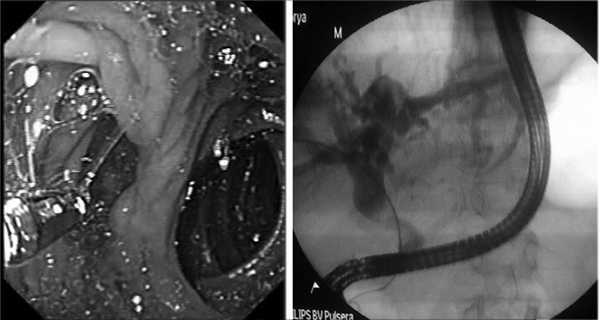

Применение методики «рандеву» (рис. 3) с низведением струны-направителя через наружную холангиостому в просвет ДПК и выполнением чреспапиллярного инструментального доступа к желчным протокам с помощью заведенной струны позволило провести окончательное малоинвазивное лечение 5 больных холедохолитиазом с наличием парапапиллярных дивертикулов I и IV типов.

Рис. 3. Доступ к желчевыводящим протокам с помощью методики «рандеву».

В 16 (3,8%) наблюдениях эндоскопические методы лечения холедохолитиаза оказались безрезультатными из-за невозможности визуализации БСДК или канюляции желчных протоков, а также выполнения чреспапиллярного дренирующего вмешательства при крупных фиксированных конкрементах общего желчного протока. В основном это были больные с одиночным крупным дивертикулом диаметром более 2 см и узким устьем. При наличии широкого устья в 3 наблюдениях попытки эндоскопического лечения с частичным заведением эндоскопа в просвет дивертикула оказались успешными (рис. 4).

Рис. 4. Доступ к желчевыводящим протокам с частичным заведением дуоденоскопа в просвет дивертикула.